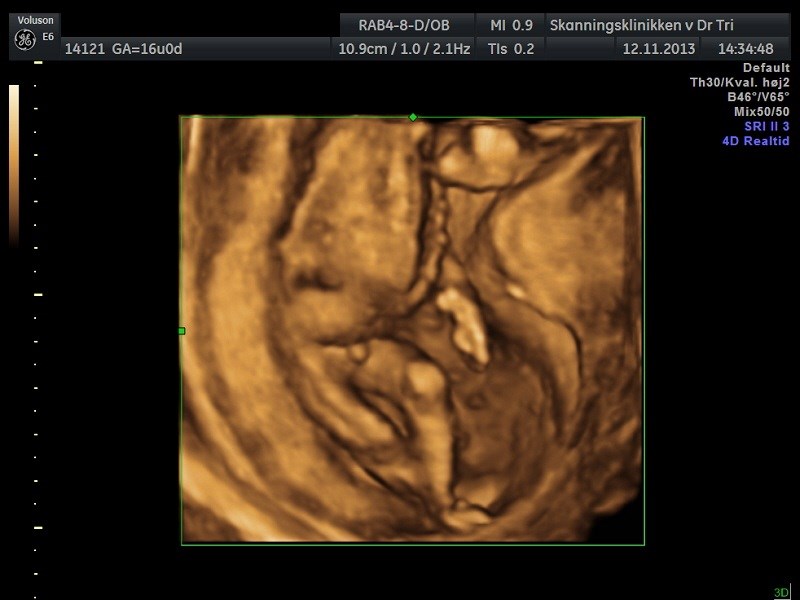

I starten var han meget blufærdig og lå med krydsede ben, men til sidst turde han godt at vise os sine private dele.

Jeg troede at det var en lille pige, som lå derinde, men jeg var åbenbart helt galt på den Så bliver det mors lille dreng i stedet for

Vi fik nogle fine billeder med hjem, og det var skønt at se, at han har det godt. Vi fik også hørt hjertelyd for første gang. Hvor var det bare skønt at få et lille kig til ham.

Vedhæftede fotos (klik for at se i fuld størrelse)